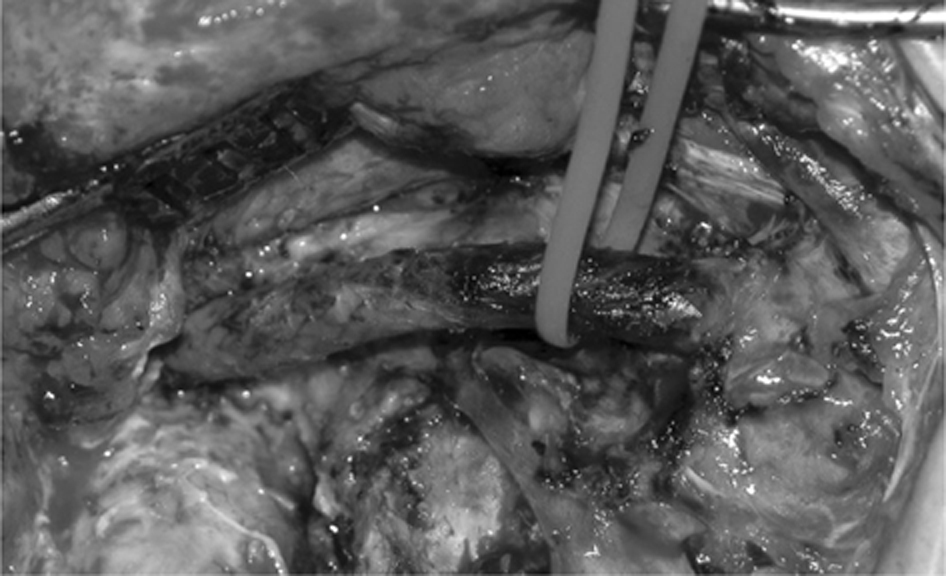

Fig 6

Figure 6 The view of the internal carotid artery. Tumor removal has been completed. Dissection has been carried out down to the stent in an almost bloodless field.